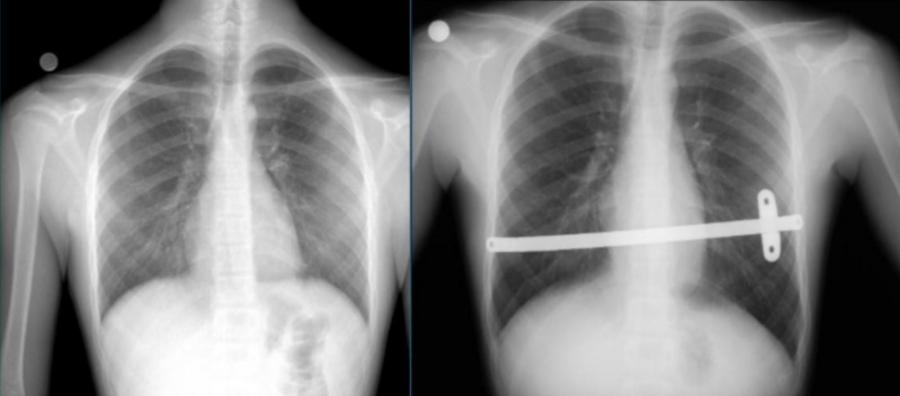

Röntgen: Kunduracı göğsü derecesinin belirlenmesi ve muhtemel ek problemleri görüntüleme amacıyla röntgen çekmekte fayda vardır.